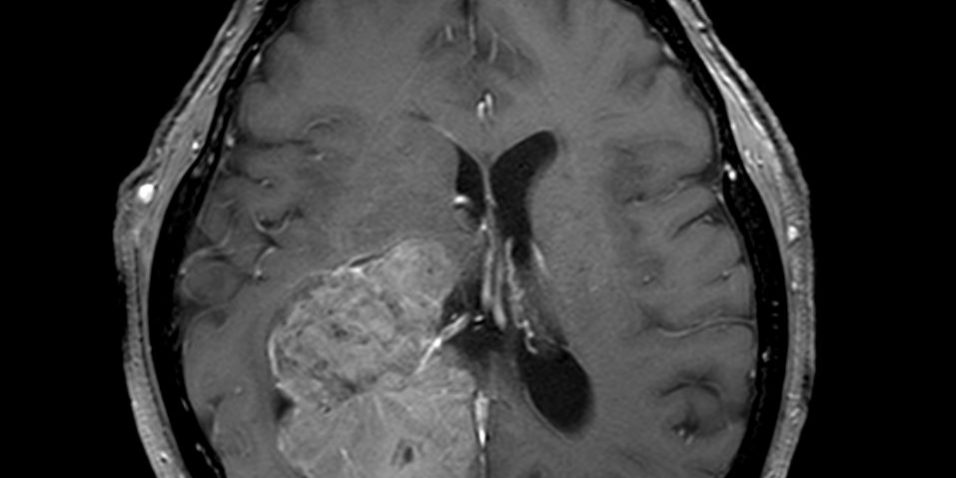

Η μαγνητική τομογραφία ανέδειξε ευμεγέθη χωροκατακτητική εξεργασία εντός της δεξιάς πλάγιας κοιλίας του εγκεφάλου.